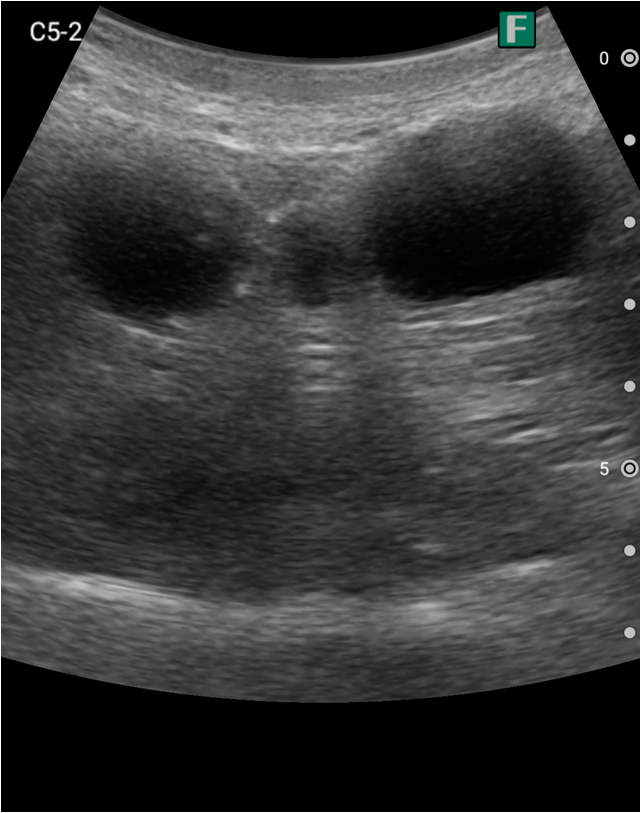

以前、私はiViz airを自分の体に当てて練習をする“セルフトレーニング”をしていました。自宅で参考書を見ながらゆっくりと時間をかけて練習できるので非常に貴重な経験を培うことができました。

据え置き型のエコーの場合、病院内の決められた場所で練習する必要があり、どうしても練習する時間が限られてしまっていました。また、横になった状態で参考書を片手に大きな装置を動かすのはかなり辛い経験でした。今回小型化されたエコーを使用できる機会を得られ、気軽に練習できるようになりエコーに触れる時間も長くなったと感じました。